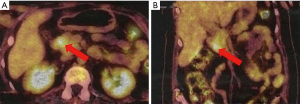

Due to the combination of physical examination findings with newly diagnosed diabetes mellitus, hypertension and severe hypokalemia, the diagnosis of Cushing syndrome was suspected. Hormonal investigations showed elevated urinary free cortisol at 11,048 nmol/day (normal range, 30–197 nmol/day) and serum cortisol at 3,146 nmol/L (normal range, 138–635 nmol/L) with an ACTH level of 126 pg/mL (normal range, 10–60 pg/mL). After 48-hour low-dose dexamethasone test, cortisol remained elevated at 2,226 nmol/L (normal range, >50 nmol/L). Subsequently, pituitary magnetic resonance imaging (MRI) excluded pituitary lesion. Therefore, the possibility of EAS was considered. Cortisol level was not suppressed even with high-dose dexamethasone suppression test thus supporting the diagnosis of EAS. Thoraco-abdominopelvic computed tomography showed just a bilateral adrenal enlargement. A whole-body scintigraphy with 111In-labeled octreotide was negative. However, positron emission tomography with fluorodeoxyglucose (18FDG-PET) revealed a hypermetabolic focus in the pancreatic head (Figure 1). Abdominal MRI was then performed. It detected a hypervascular well-defined mass at the level of pancreatic uncinate process measuring 10 mm × 10 mm highly suspicious for a pancreatic NET with no evidence of distant metastases. Endoscopic ultrasound-guided biopsy of the pancreatic lesion showed a well-differentiated NET with a Ki-67 of less than 1%. On immunohistochemical analysis, tumor cells were positive for chromogranin, synaptophysin and ACTH (Figure 2), confirming the pancreatic tumor as the source of ectopic ACTH. The tumor was graded as grade 1 on World Health Organization (WHO) 2017 classification.

The diagnosis of PCS caused by ACTH-producing NETs is based on vigorous hormonal evaluation (high-dose dexamethasone suppression test, corticotrophin-releasing hormone or desmopressin stimulation test, bilateral petrosal sinus sampling), imaging exploration using pituitary MRI, thoraco-abdominopelvic computed tomography, somatostatin receptor scintigraphy (OctreoScan, Polatom, Poland) and 18FDG-PET, which is far less widely used (17,24); and histological findings (25). The place of 18FDG-PET in localization of ectopic ACTH-secreting tumors is still controversial. Xu et al. (26) reported that the use of integrated 18FDG-PET and computed tomography was useful in the localization of ACTH-secreting tumors in five patients in whom conventional imaging were negative. Surgical removal of detected lesions (FDG uptake) led to normalization of both ACTH and cortisol levels. Moreover, according to a systematic review published by Isidori et al. (27); 18FDG-PET is more sensitive than OctreoScan for detection of abdominal lesions. Our patient had a negative OctreoScan, however, 18FDG-PET was able to locate the lesion.